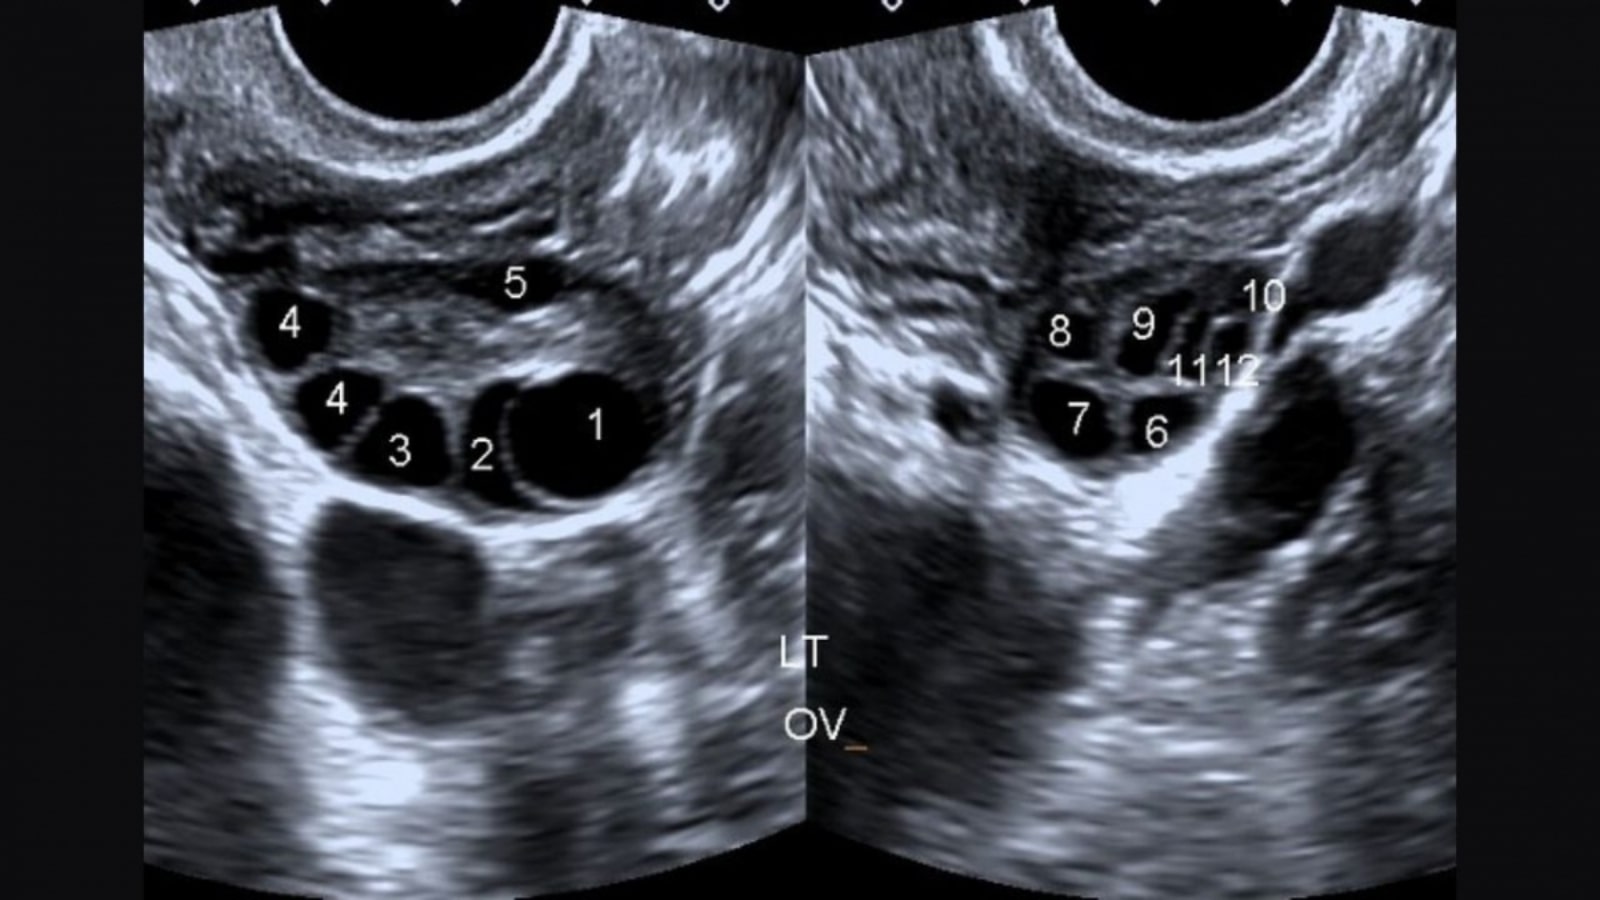

- Các nang nhỏ trên buồng trứng qua siêu âm

- Hình ảnh siêu âm cho thấy buồng trứng đa nang

Các xét nghiệm cần thiết để chẩn đoán chính xác bao gồm đo nồng độ hormone testosterone, LH, FSH, AMH, glucose và insulin lúc đói. Siêu âm buồng trứng qua âm đạo cũng là phương pháp quan trọng để đánh giá cấu trúc buồng trứng.

Quy trình theo dõi siêu âm định kỳ trong quá trình điều trị rất quan trọng để đánh giá phản ứng của buồng trứng và điều chỉnh liều thuốc phù hợp.